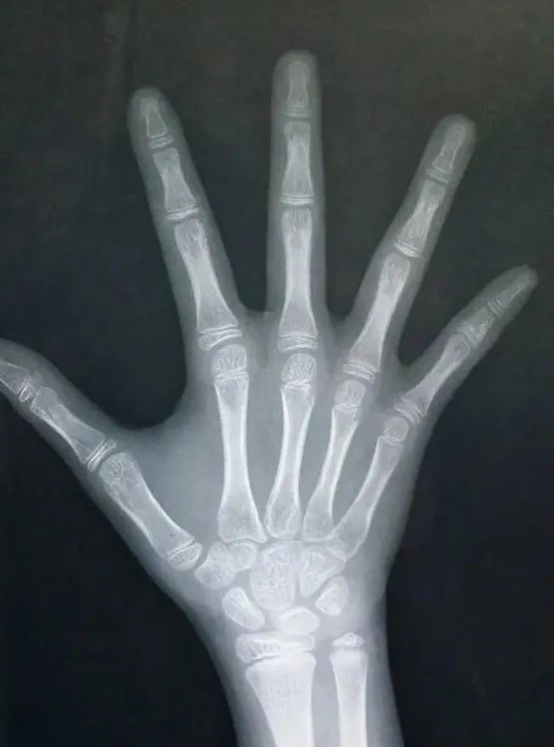

如何评估骨龄?

不同阶段的骨头具有不同的形态特点。通常利用左手手腕部X线摄片,根据腕骨、掌骨、指骨骨化中心数量、大小、形态、以及结构相互关系来确定骨龄。